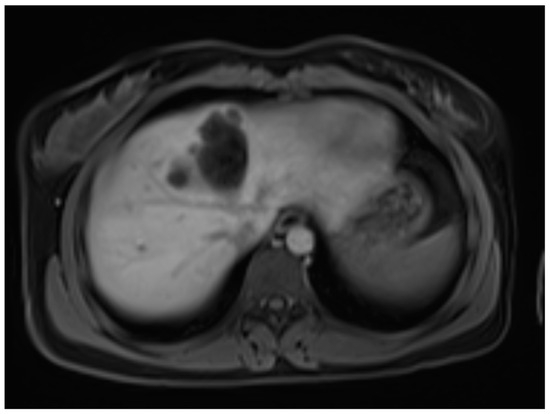

Six months later, a second ultrasound scan and a consecutive MRI scan to follow-up and control the success of the therapy were performed. The ultrasound revealed a decrease in the size of the cyst from 10 cm in maximal diameter to 9 cm and showed multiple circular septations, indicating an involuting cyst (Figure 7). In contrast to the preceding MRI scan, typical T2 hypointense membrane-like structures were observed within the lesion in T2WI. These represented most probably the floating membranes, the typical water-lily sign (Figure 8). T1WI (Figure 9) showed the cyst as a hypointense lesion, but the membranes could only be clearly observed in T2WI. Consecutively, the cyst was classified as WHO-CE3A.

Second MRI scan: Axial T1W native MRI scan, where the floating membranes are rather difficult to depict, with the hypointense area in liver segment IV showing the cyst.